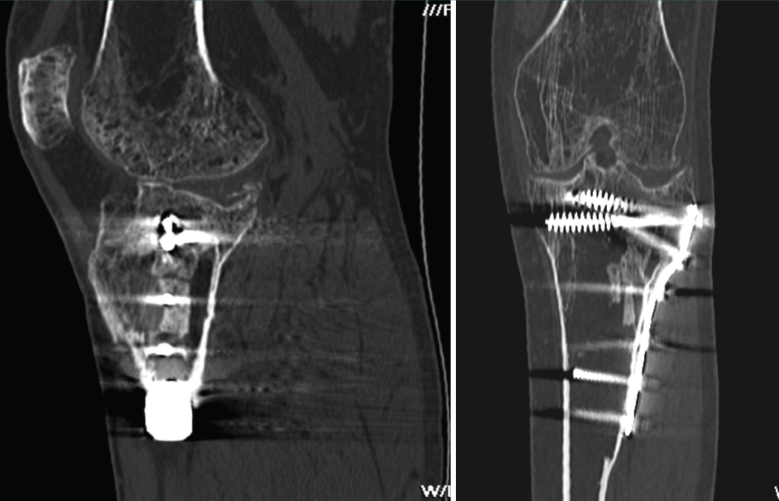

1.1. Fémur (Figuras 18 y 19)

Figura 18. A: corte de reconstrucción coronal; B: axial; y C: reconstrucción 3D de tomografía axial computarizada de rodilla: fractura longitudinal del fémur extendida al techo intercondilar.

Figura 19. Corte de reconstrucción sagital y coronal de tomografía axial computarizada de rodilla: fractura de Hoffa del fémur, del cóndilo femoral externo, de difícil diagnóstico en las radiografías.